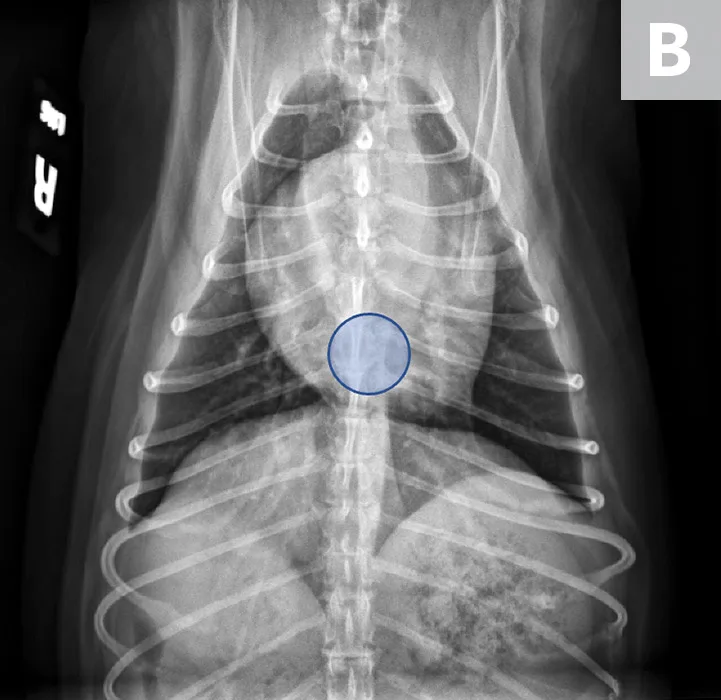

FIGURE 1

VLAS measurement in a dog with suspected stage B1 MMVD using a left lateral radiograph (A). A caliper was used to measure from the center of the most ventral aspect of the carina to the most caudal aspect of the left atrium, where it intersects with the dorsal border of the caudal vena cava. This measurement was transferred to the cranial aspect of T4 and extended caudally along the thoracic vertebrae. The number of vertebrae this line transversed was rounded to the nearest tenth to determine VLAS (2.1 VBUs). Stage B1 MMVD was confirmed via echocardiography. A redundant dorsal tracheal membrane, gastric food/foreign material, and mild T3 to T4 spondylosis deformans can also be seen. An orthogonal radiograph of the patient provides a more complete evaluation of cardiac silhouette (B); normal location of the left atrium is indicated (circle).